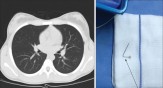

11-കാരിയുടെ ശ്വാസകോശത്തില് കുടുങ്ങിയ പിന് പുറത്തെടുക്കാനായത് ആറാംനാള്, ശിരോവസ്ത്രത്തില് കുത്തുന്നതിന് കടിച്ചുപിടിച്ചിരുന്നതിനിടെ വിഴുങ്ങിപ്പോയതാണ്!

ശിരോവസ്ത്രം ധരിക്കുന്നതിനിടെ കടിച്ചുപിടിച്ചിരുന്ന പിന് അറിയാതെ വിഴുങ്ങിപ്പോയ ബാലിക പിന്നീടുള്ള ആറു ദിനങ്ങള് തള്ളിനീക്കിയത് ജീവിതത്തിനും മരണത്തിനുമിടയിലെ നൂല്പാലത്തിലൂടെ. നവംബര് 21-നാണ് 118-കാരിക്ക...